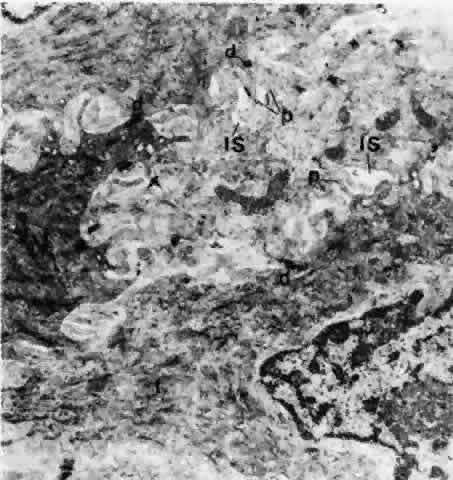

Fig. 10. Middle layer of bulbar conjunctival epithelium showing widened intercellular spaces, into which small cytoplasmic processes are protruding. Relatively few desmosomes are shown. Tonofilaments (t) tend to form bundles. IS, intercellular space; d, desmosomes; p, cytoplasmic processes. (× 20,800)